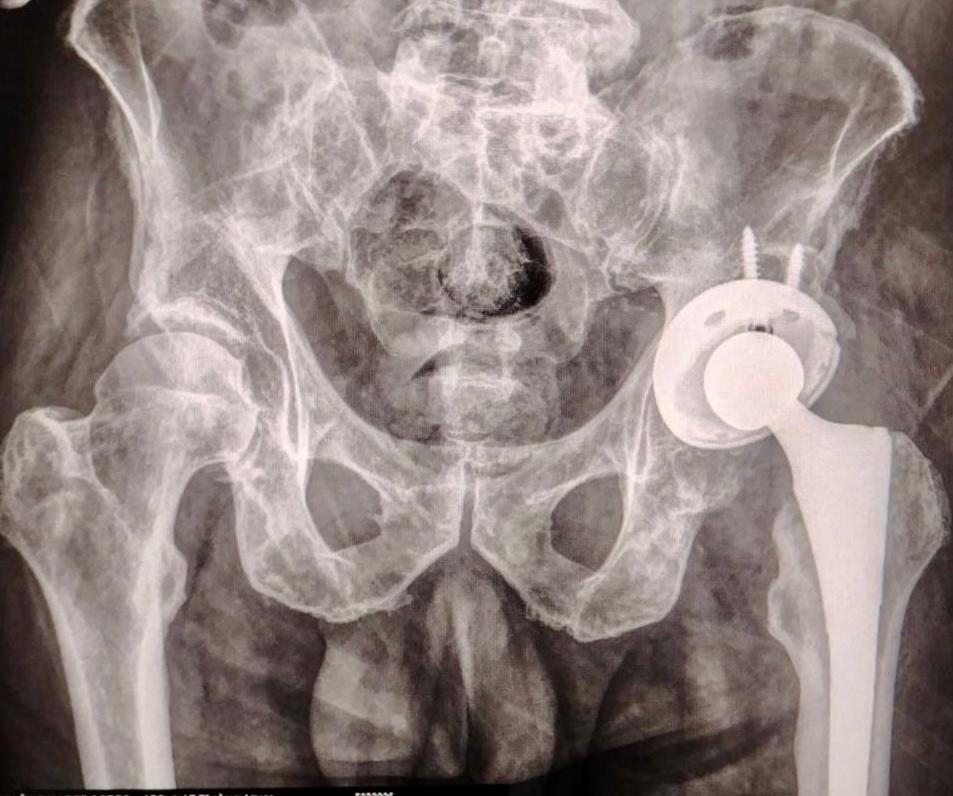

La intervención fue realizada por un equipo multidisciplinario altamente capacitado, siguiendo estrictos protocolos de seguridad y criterios clínicos rigurosos, en un acto que refleja la innovación tecnológica aplicada a la atención integral de enfermedades osteoarticulares. La cirugía permitió a un paciente con desgaste severo recuperar su movilidad y mejorar su calidad de vida, en línea con la política de la bioética social que promueve el gobernador Armenta para garantizar la seguridad en salud sin barreras económicas.

El Programa de Cirugía Articular, que ha iniciado en el ISSSTEP, busca ofrecer alternativas de tratamiento quirúrgico de nivel mundial, asegurando la seguridad en todas las etapas, desde la preoperatoria hasta el seguimiento postoperatorio. La inversión en tecnologías avanzadas y la capacitación del personal quirúrgico fortalecen este modelo, que va creciendo para beneficiar a más derechoshabientes.